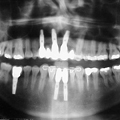

Films radiographiques oraux

Les films radiographiques sont utilisés dans les cliniques dentaires pour réaliser des radiographies intrabuccales. Ces films peuvent être de tailles et de formes différentes et présenter des caractéristiques de traitement et de manipulation divers afin de répondre aux besoins variés du dentiste.